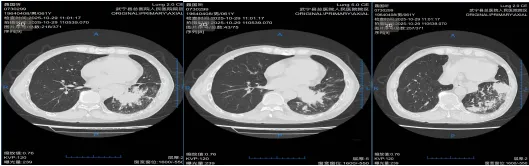

二、胸外科:高难微创,勇克双侧多原发肺癌

胸外科在复杂肺癌手术领域不断突破。一例55岁女性患者,CT发现双肺多发结节,高度怀疑多原发肺癌。面对传统分期手术创伤大、恢复慢的挑战,经多学科(MDT)充分评估、精密协作,胸外科团队勇于创新,成功为患者实施了“单孔胸腔镜下同期双侧肺癌根治术(右肺上叶切除+左肺下叶背段切除+双侧纵隔淋巴结清扫)”。手术一次完成,极大减少了患者痛苦与住院时间。术后病理证实为双侧原发性肺癌,分期分别为IIB期和IA2期。患者术后恢复迅速,第二天即可下床活动,并接受规范的靶向治疗(口服奥希替尼)。至今随访2年,无复发迹象,生活质量高。此案例彰显了我院胸外科在高难度、微创化、个体化肺癌手术治疗方面的卓越实力。

术前右侧胸部肿瘤

术前左侧胸部肿瘤

术后病理及免疫组化